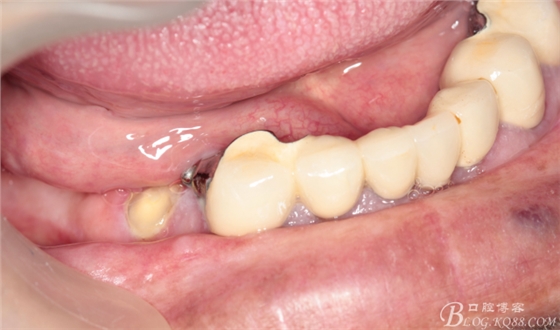

下頜由于44治療之后,松動(dòng)度改善不大,原來(lái)的咬合創(chuàng)傷比較大,不能承擔(dān)較大的(牙合)力,選擇覆蓋義齒,把它磨短平齊牙齦,

其他牙比較集中,選擇雙端球帽式附著體修復(fù)雙端游離缺失

修復(fù)后效果圖,